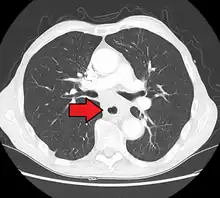

Esophageal cancer as shown by a filling defect during an upper GI series

Although an occlusive tumor may be suspected on a barium swallow or barium meal, the diagnosis is best made with an examination using an endoscope. This involves the passing of a flexible tube with a light and camera down the esophagus and examining the wall, and is called an esophagogastroduodenoscopy. Biopsies taken of suspicious lesions are then examined histologically for signs of malignancy.

Additional testing is needed to assess how much the cancer has spread (see #Staging, below). Computed tomography (CT) of the chest, abdomen and pelvis can evaluate whether the cancer has spread to adjacent tissues or distant organs (especially liver and lymph nodes). The sensitivity of a CT scan is limited by its ability to detect masses (e.g. enlarged lymph nodes or involved organs) generally larger than 1 cm.[41][42] Positron emission tomography is also used to estimate the extent of the disease and is regarded as more precise than CT alone.[43] Esophageal endoscopic ultrasound can provide staging information regarding the level of tumor invasion, and possible spread to regional lymph nodes.